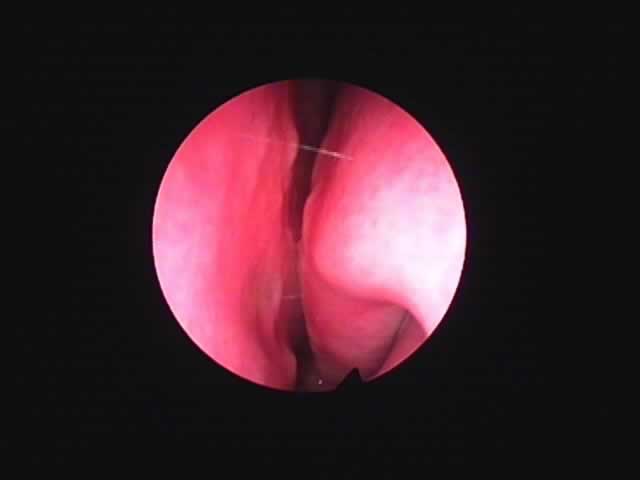

| 左扁桃術直後(31歳男性,6月9日) 数カ所針電極を刺入 | 白い部分が変性部位(6月11日) | 右扁桃術直後(7月7日) |